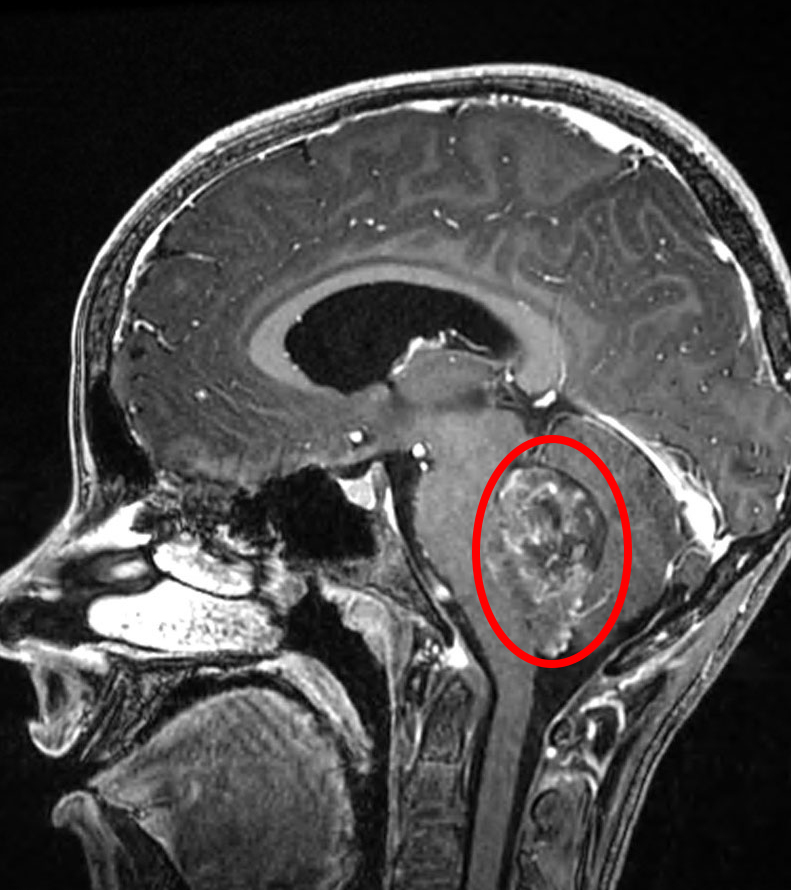

What is medulloblastoma?

tumor that arises from primitive (highly undifferentiated) cells in the cerebellum (midline)

How does medulloblastoma grow?

4 Signs and symptoms of medulloblastoma?

speech difficulties

balance issues

hydrocephalus

early morning vomitting

Yes! its more common than other brain tumors

Where does medulloblastoma spread to (mets)?

How is Medulloblastoma treated?

Surgery and adjuvant radiation therapy (CSI and boost to posterior fossa)